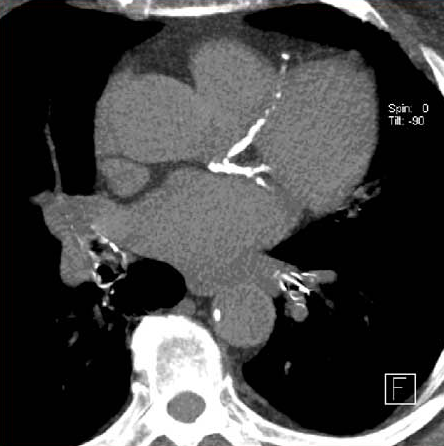

Neumonía adquirida en la comunidad: una revisión

La neumonía adquirida en la comunidad es común y puede provocar sepsis, síndrome de dificultad respiratoria aguda o muerte. El tratamiento de primera línea varía según la gravedad y la etiología de la enfermedad. Los pacientes hospitalizados con sospecha de NAC bacteriana y sin factores de riesgo de bacterias resistentes pueden ser tratados con una terapia combinada de β-lactámicos/macrólidos, como ceftriaxona combinada con azitromicina, durante un mínimo de 3 días. JAMA, 16 de septiembre de 2024.